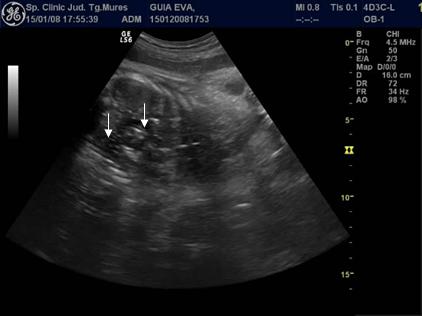

Fig. nr. 237. Incalecarea oaselor craniului la un fat mort macerat , 34 sapt.

Fig. nr. 239 Aparitia de bule in cavitatile toracica si abdominala ( sageti ), dupa maceratie la fatul mort intrauterin , la 34 sapt.